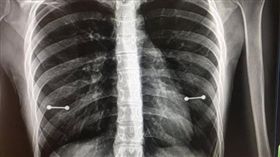

她照X光驚見胸前2條槓!媽媽秒變臉

美國佛州一名20歲女子藏有小秘密,日前她偷偷去穿乳環...

少女照X光驚見「2條槓」!媽超火大

美國佛州一名妙齡女子藏有小秘密,在去年6月去穿乳環,...

她X光驚見乳頭「2條槓」!媽媽怒了

美國佛州一名20歲女子藏有小秘密,在今年6月去穿乳環...